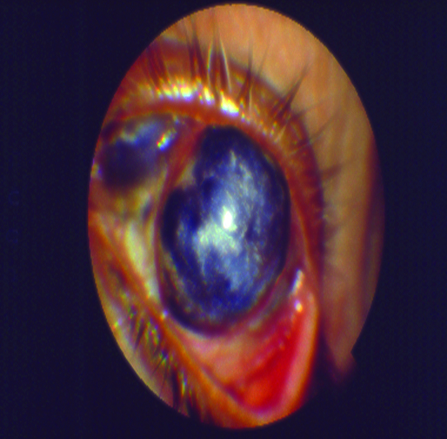

5) Tratamiento quirúrgico:

El tratamiento quirúrgico se enfoca específicamente en la reparación del posible daño severo que el ojo seco y generalmente sus patologías sistémicas asociadas pudieran haber provocado sobre la superficie ocular (Fig. 19).

Figura 19: Daño severo de la superficie ocular

Dentro del tratamiento quirúrgico se encuentran los injertos de limbo, los injertos de amnios y las queratoplastias.